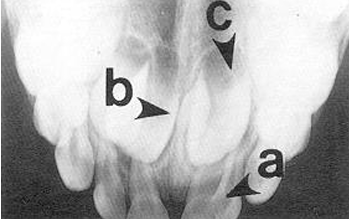

occlusal radiographs

occlusal v. periapical radiographs

-occlusal: can often visualize the whole arch, angulation can vary

-periapical: a section of the arch that shows the whole tooth crown to apex- position film as if taking an occlusal

-maxillary and mandibular occlusals